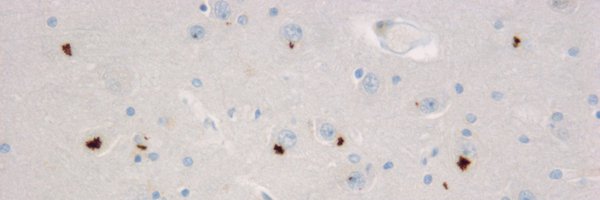

TDP-43 CTF forms gel-like inclusions and sequesters stalled proteasomes in neurons. #ALS mutants impair proteostasis even more. #CryoET study with @ruferbus and @QiangGuo_EM.

biorxiv.org

TDP-43 inclusions enriched in C-terminal fragments of ~25kDa (“TDP-25”) are associated with neurodegeneration in amyotrophic lateral sclerosis (ALS) and frontotemporal dementia (FTD). Here, we...